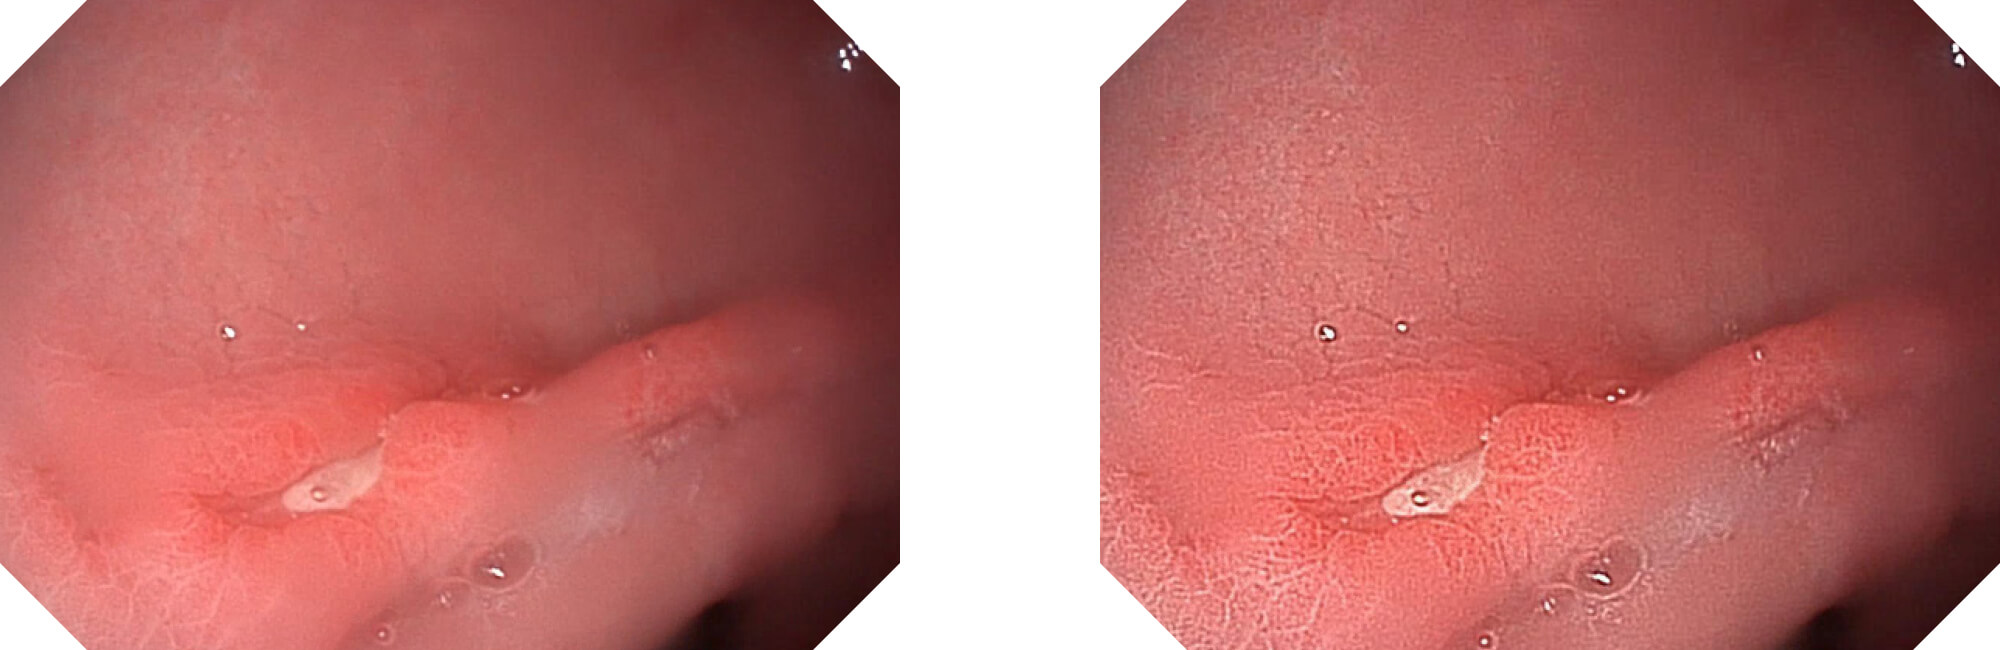

电子放大

(Versatile Intelligent Staining Technology)

利用了血红蛋白在不同波长吸收下系数不同的原理,设计的一种光学域滤波和数字域滤波结合的染色技术,既保证了图像亮度,又可增强黏膜血管的对比度,充分凸显早期病变的细微结构变化,为临床疾病的观察诊断提供更丰富的参考信息。